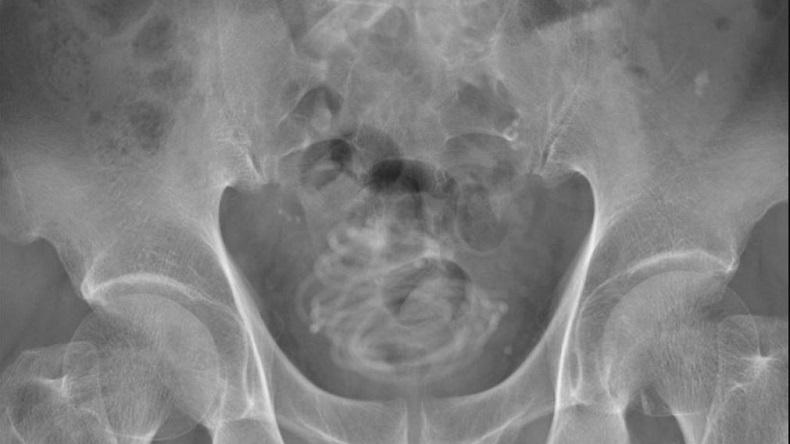

Selanjutnya, tim dokter melakukan rontgen. Hasilnya, mereka menemukan benda asing melingkar seperti kawat di dalam kandung kemih.

Model 3D bagian dalam kandung kemih pria itu harus dibuat untuk membantu petugas medis memetakan prosedurnya.